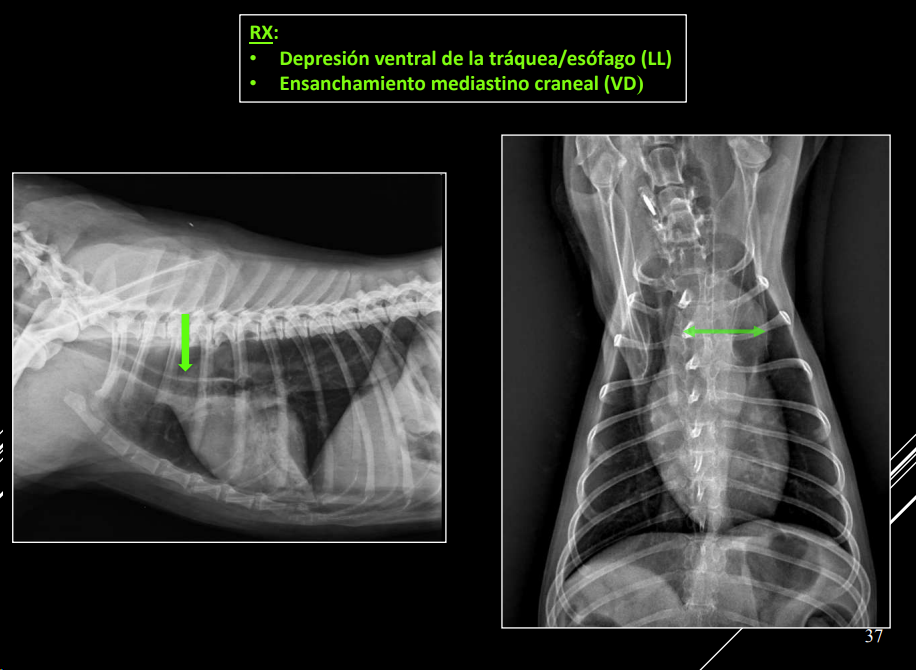

3. Alteraciones de anchura del mediastino craneal

- En perros: anchura < 2x VT.

- En gatos: anchura ≈ VT.

- En braquicéfalos/obesos puede verse mayor (grasa mediastínica).

- Generalmente en gatos es por un linfoma.

Causas:

- Derrame mediastínico.

- Masas mediastínicas (craneodorsales, hilares, caudodorsales, caudoventrales, craneoventrales).

- Linfomas en gato, timomas en perros.

Desplazamiento traqueal ventral por neumoesofago

Desplazamiento traqueal dorsal por masa en el mediastino craneal